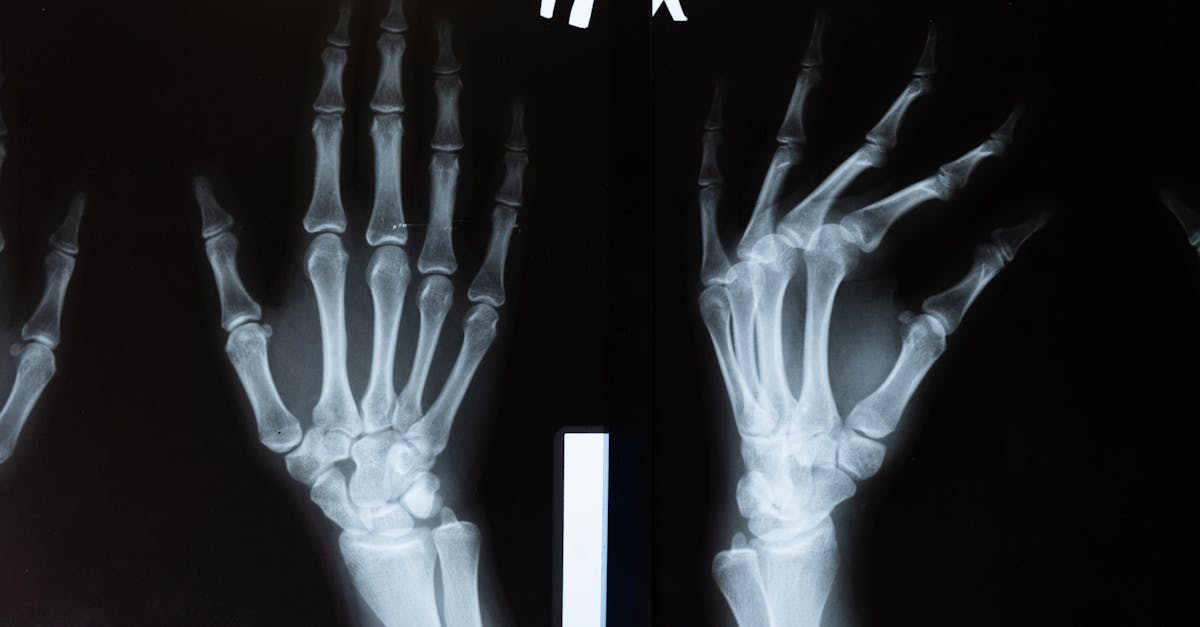

Imaging plays a crucial role in monitoring the progress of various medical treatments. It allows healthcare professionals to visualize the internal changes in a patient's body over time, providing valuable insights into the effectiveness of the treatment being administered. By utilizing imaging techniques such as X-rays, MRI, and CT scans, doctors can track the response of tumors to chemotherapy, evaluate the healing of fractures, or observe the reduction in inflammation post-treatment.

Imaging plays a crucial role in forensic investigations by providing detailed visual evidence that can aid in solving crimes and unraveling mysteries. From capturing precise images of crime scenes to documenting injuries on victims, imaging technology allows forensic experts to gather essential information that can be used in court proceedings. For example, digital imaging techniques enable forensic investigators to meticulously document physical evidence, such as fingerprints, footprints, or weapons, ensuring that critical details are recorded accurately for further analysis.

Imaging techniques can detect various abnormalities, diseases, injuries, and changes within the human body by creating visual representations of internal structures and functions.